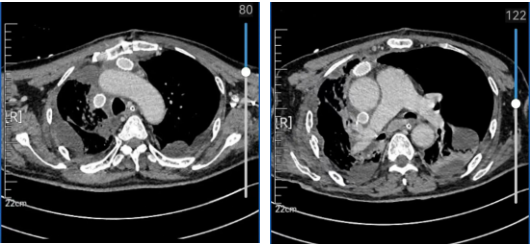

66岁的男性患者罹患纵隔肿瘤多方求医,因肿瘤侵犯大血管而屡次遭拒,几经辗转后到我院胸外科住院治疗。入院并完善相关检查后,诊断为胸腺癌,累及心包、上腔静脉、左无名静脉、右肺上叶。

术中先实施了剑突下胸腔镜的探查和部分游离探明肿瘤范围和侵犯深度。随后纵劈胸骨开胸,行左无名静脉置换术(左无名与右心耳桥接),切除部分心包及右侧膈神经,行右侧膈肌折叠术。右侧开胸切除右肺上叶,并行上腔静脉置换术。术中实施全身及局部肝素化,防止血栓形成。在麻醉科医师李国华,洁净手术部李婷婷、卜晓霞护士的配合下,手术历经5个小时,顺利完成。术后患者带气管导管安全返回ICU治疗。目前,在重症医学科主任段燕团队的努力下,患者为自主呼吸模式,凝血、心功能基本正常,血管彩超未见明显栓塞。